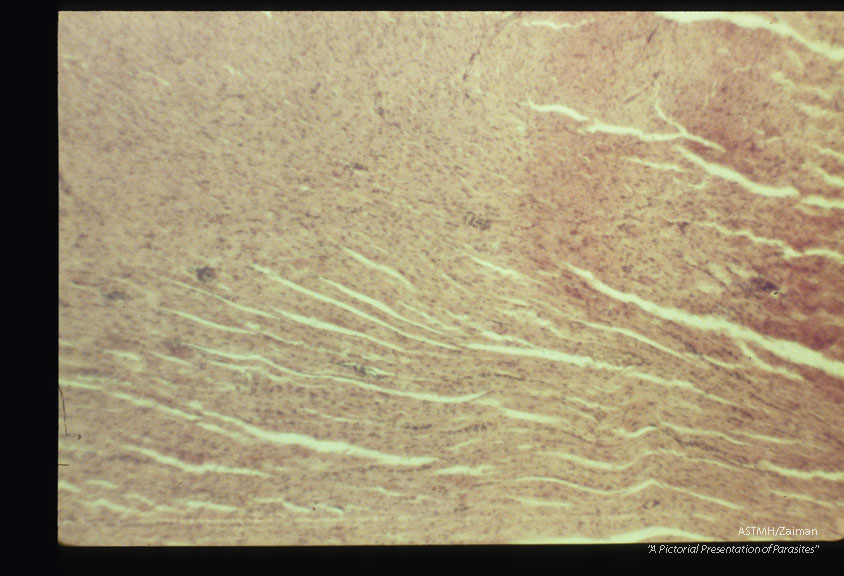

Diffuse inflamatory lesion. Experimental trichinous myocarditis in rats.

Trichinella spiralis

Description: Diffuse inflamatory lesion. Experimental trichinous myocarditis in rats.